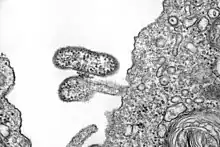

| electron microscope image of Chapare virus | |

The Chapare virus is an enveloped virus with a bi-segmented single-stranded ambisense RNA genome. The two RNA segments are denoted Small (S) and Large (L). It belongs to the New World Clade B lineage of mammarenaviruses and is most closely related to the Sabia virus.[2][5]